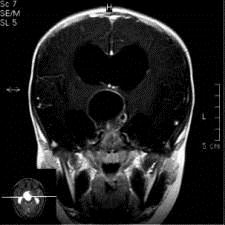

问题 病历摘要:??患者女性,6岁,半年来感觉视力模糊,近10天出现反复头痛,间有恶心呕吐,精神转差,查体:神志清楚,身高90cm,体重25Kg,血压90/55mmHg,右眼视力4.6,左眼视力4.8,双侧视乳头水肿,颈软,伸舌居中,四肢肌张力正常,肌力5级,双侧Babinski征(-)。 手术利用右侧翼点入路,在显微镜下利用鞍区自然间隙进行,一般来说,第二间隙可以窥见的结构有?

选项 A.右侧视神经 B.右侧大脑前动脉 C.前交通动脉 D.垂体上动脉 E.Heubner?回返动脉 F.颈内动脉床突上段 G.基底动脉 H.右侧小脑前下动脉

答案 ADFG

解析 ADFG